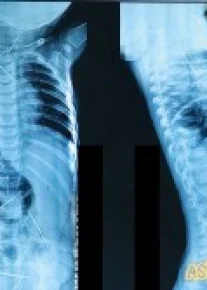

Эслатиб ўтамиз, аввалроқ Фарғона вилоятида истиқомат қилаётган ёш оиланинг 11 ойли чақалоғи танасидан 16 дона игна топилгани хабар берилганди. Республика шошилинч тиббий ёрдам илмий марказига келтирилган бола тезкорлик билан жарроҳлик столига ётқизилган. Игналардан 13 таси олиб ташланган. Бу пўлат жисмлар гўдак танасида 2 ой муқаддам пайдо бўлганлиги аниқланган. Таъкидланишича, барча игналар танада турлича жойлашган: уларни чақалоқнинг йўғон ичак қисмида, сийдик қопи, кўкрак қафасида, боланинг бўйин қисмида, умуртқа поғонасида, юрак остида топилган. Шифокорларнинг фикрича, 11 ойли чақалоқ ҳеч қачон бунча кўп металлни ютиб юбориши мумкин эмас, қолаверса, қизилўнгач ва ошқозонда ҳеч қандай йиртиқ аломати топилмаган. Биргина фаразни илгари суриш мумкин, игналар тана ташқарисидан, онгли равишда терига тиқилган.